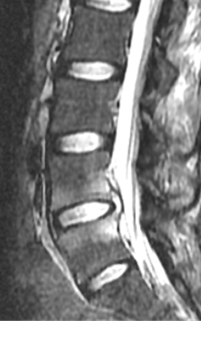

32 years old lady presented with worsening back pain for 4 weeks duration following elective caeseran section done for malpresentation. There was history of repeated attempts of puncture for spinal anaesthesia . She was cathetrised which was removed on day 2 and she has received intravenous broad spectrum antibiotics for 5 days duration. Her surgical wound healed well with no documentation of fever, abdominal pain, cough, dysuria or discharge per vaginum. At presentation her pain was predominantly in lower lumbar region ( VAS – 9/10) with severe paraspinal muscle spasm. She was not able to sit for few minutes and had difficulty in turning in bed . she couldn’t nurse her child due to pain with inability to assume comfortable postures. Root tension signs were negative with no neurological deficits. Radiographs revealed L3/4 disc space reduction with end plate changes. Hematological evaluation showed  elevated TLC, ESR,CRP ( Table 1) . Septic screening for urine , blood and chest infection was negative. MRI showed evidence of spondylodiscitis at L3/4 (FIG 5,6) . She underwent CT guided biopsy which was negative. She later underwent PLIF L3/4 and had grown pseudomonas from the necrotic disc material sent for culture & sensitivity. She was mobilized on day -1 with lumbo sacral brace. Her low back pain reduced significantly ( VAS -2/10) and she needed minimal analgesics ( single dose of intravenous paracetamol ) for one week.  She had 2 weeks of intra venous Cefaperazone + sulbactum followed by 4 weeks of oral antibiotics. Radiographs showed fusion by 3 months ( FIG 7,8) and hematological parameters normalized by 6 weeks.(Table 1)

Fig 5: T2 MRI – L3/4 spondylodiscitis

Fig 6: T1 MRI – L3/4 spondylodiscitis